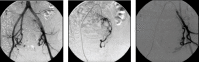

Introduction: Uterine leiomyomas are the most common benign pelvic tumors in women over 35 years and can be symptomatic or asymptomatic. Among the main treatment strategies, there are hormone therapy, hysterectomy, myomectomy, and uterine artery embolization (UAE), a recent and promising treatment for patients who wish to avoid hysterectomy. Ideal candidates for UAE are women with symptomatic uterine leiomyomas that present no desire for pregnancy, premenopausal and heavy menstrual bleeding, or dysmenorrhea caused by intramural fibroids. Case Presentation. A 36-year-old female diagnosed with leiomyomas and an extensive history of failed previous treatments who, in order to preserve her uterus, underwent UAE and had tumor expulsion 15 days after the procedure. The patient remained eight months in amenorrhea and, currently, presents normal hormone levels and irregular periods.